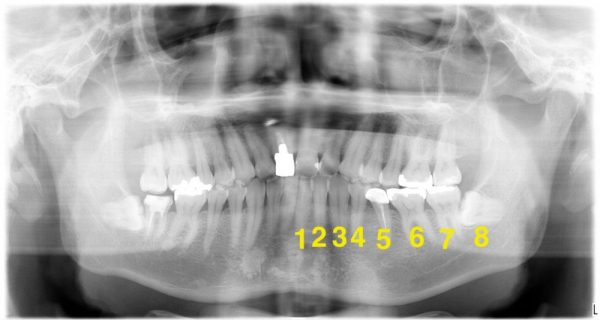

親知らずは、真ん中の歯から数えて8番目の歯です。

この画像で傾いているのが親知らずです。親知らずと7番目の歯の間に汚れが入り、虫歯と歯周病になっています。

この画像で傾いているのが親知らずです。親知らずと7番目の歯の間に汚れが入り、虫歯と歯周病になっています。